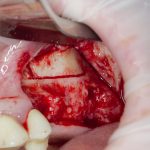

Простой синуслифтинг. Часть I.